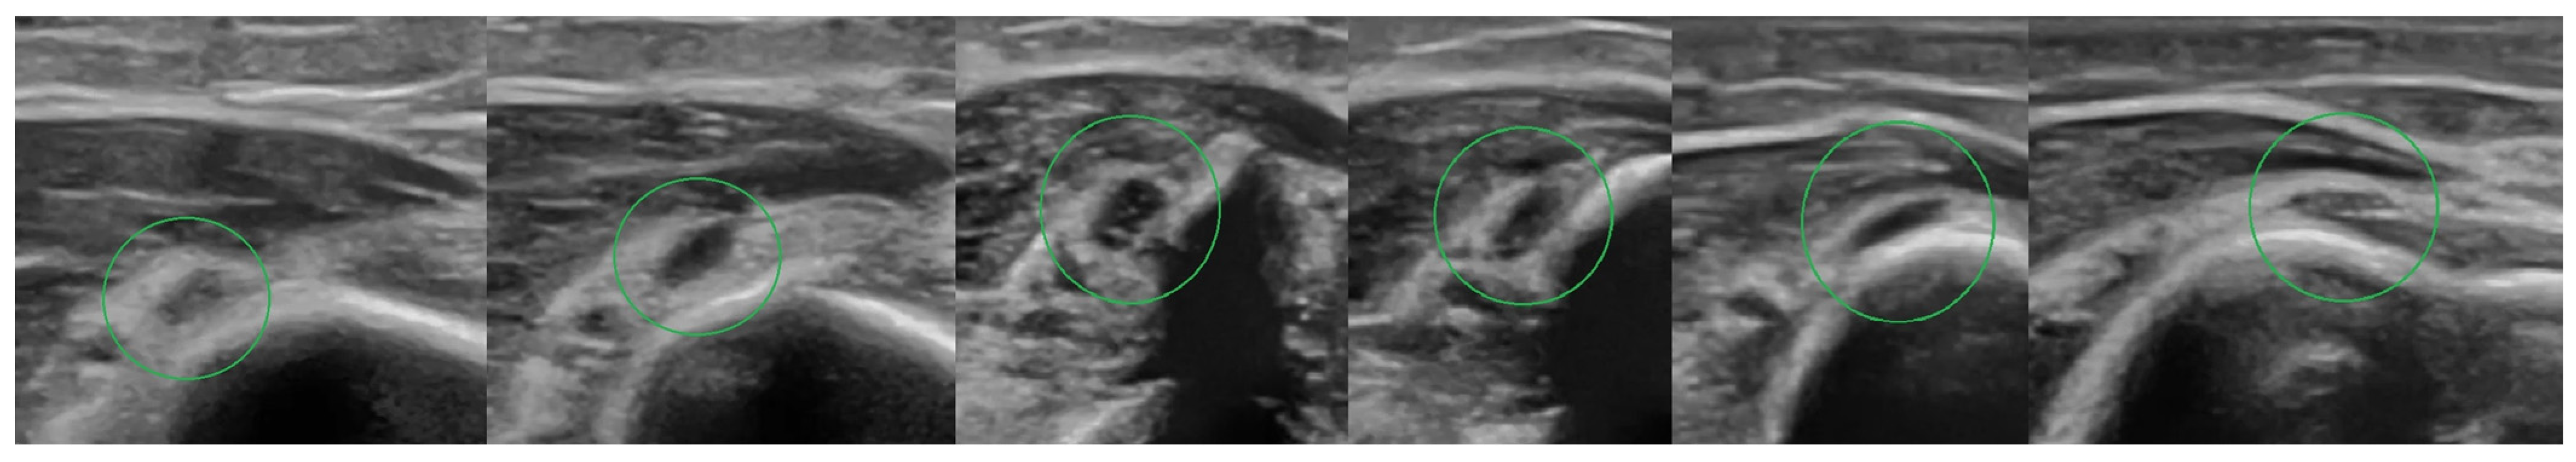

4.2. Ultrasound Examination